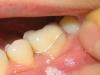

DOK Elena Опубликовано 26 июня, 2008 Поделиться Опубликовано 26 июня, 2008 (изменено) Пациентка была направлена мной к ортопеду после окончания ортодонтического лечения. ортодонту не удалось довести 36 до контакта с 26 по 1 классу ( в результате 36 завален язычно ). 36 имел ранее поставленную пломбу 1 класс без претензий к качеству и рецидива. приняли решение изготовить вкладку из оксида циркония в 36 для восстановления контакта с 26. с точки зрения ортодонта изготовленная вкладка воссоздает контакт с антогонистом идеально, бугры там тоже отличные. Но есть одно сомнение : соответствует ли это все эстетике и что в таких случаях вообще считается допустимым по красоте. пациентка недовольна. пломба, по ее мнению, была красивее. На приложенных фото вкладка фиксирована на временном цементе. что думаете, переделывать? техник говорит, что лучше не сделает.... ( имеется ввиду вестибулярная поверхность вкладка-зуб ). Может какую-то другую конструкцию делать? И можно ли вообще в таких случаях сделать переход от вкладки к эмали зуба незаметным? Изменено 26 июня, 2008 пользователем DOK Elena Ссылка на комментарий

Fred Опубликовано 26 июня, 2008 Поделиться Опубликовано 26 июня, 2008 Пациентка была направлена мной к ортопеду после окончания ортодонтического лечения. ортодонту не удалось довести 36 до контакта с 26 по 1 классу ( в результате 36 завален язычно ). 36 имел ранее поставленную пломбу 1 класс без претензий к качеству и рецидива. приняли решение изготовить вкладку из оксида циркония в 36 для восстановления контакта с 26. с точки зрения ортодонта изготовленная вкладка воссоздает контакт с антогонистом идеально, бугры там тоже отличные. Но есть одно сомнение : соответствует ли это все эстетике и что в таких случаях вообще считается допустимым по красоте. пациентка недовольна. пломба, по ее мнению, была красивее. На приложенных фото вкладка фиксирована на временном цементе. что думаете, переделывать? техник говорит, что лучше не сделает.... ( имеется ввиду вестибулярная поверхность вкладка-зуб ). Может какую-то другую конструкцию делать? И можно ли вообще в таких случаях сделать переход от вкладки к эмали зуба незаметным? Вкладкой, наврядли, получится сделать незаметный переход ... Особенно, из диоксида циркония, у которого не только оптические свойства очень сильно отличаются от оптических свойств зуба, но и с адгезией проблемы. Ссылка на комментарий

Гость Vini Vidi Vici Опубликовано 27 июня, 2008 Поделиться Опубликовано 27 июня, 2008 А нельзя чуть по-другому отпрепарировать вестибулярную поверхность и отправить-таки на переделку?Ещё с цветом немного не попали в линии перехода. Ссылка на комментарий

Гость Vini Vidi Vici Опубликовано 27 июня, 2008 Поделиться Опубликовано 27 июня, 2008 Вы имеете ввиду совсем убрать вестибулярку?Ну не совсем, просто сделать уступ-и хорошо снять слепок. И про переход помнить. Ближе к шейке цвет не тот. Ссылка на комментарий

IgorD Опубликовано 27 июня, 2008 Поделиться Опубликовано 27 июня, 2008 если уступ на уровне или ниже десневого края это разве не обычная коронка? коронка, это когда мы изготавливаем коронку зуба полностью... а все остальное имеет названия - типа полукоронка, или коронка 2\3 или 7\8... подробнее у Шиллинбурга... ... Ну не совсем, просто сделать уступ-и хорошо снять слепок. И про переход помнить. Ближе к шейке цвет не тот.вестибудярку надо убирать совсем, вот уступ можно под десну не опускать глубоко... или сделать на уровне десны... иначе эстетики не будет... "в стык" в цвет попасть получается не всегда... ведь кроме цвета еще есть масса факторов влияющих на Эстетику... З.ы. увас композитом "в стык" получится сделать невидимый переход? ... думаю что нет.... Ссылка на комментарий